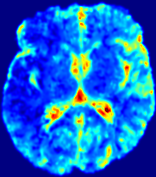

LesionRefer to captionRefer to captionRefer to captionRefer to captionRefer to captionRefer to caption𝐕rgbsubscript𝐕𝑟𝑔𝑏{\bf{V}}_{rgb}Refer to captionRefer to captionRefer to captionRefer to captionRefer to captionRefer to caption𝐕2subscriptnorm𝐕2{\|\bf{V}}\|_{2}Refer to captionRefer to captionRefer to captionRefer to captionRefer to captionRefer to captionRefer to caption3.53.53.52.82.82.82.12.12.11.41.41.40.70.70.70.00.00.0(mm/s)𝑚𝑚𝑠(mm/s)D𝐷DRefer to captionRefer to captionRefer to captionRefer to captionRefer to captionRefer to captionRefer to caption0.0200.0200.0200.0160.0160.0160.0120.0120.0120.0080.0080.0080.0040.0040.0040.0000.0000.000(mm2/s)𝑚superscript𝑚2𝑠(mm^{2}/s)Slice #1Slice #2Slice #3Slice #4Slice #5Slice #6

Figure 3: PIANO feature maps for one stroke patient, where the lesion is located in the left hemisphere. Top row: segmented stroke lesion region (white) on different slices, obtained from ISLES 2017. The corresponding slices for the PIANO feature maps are shown in the following rows.

For a better insight into an estimated velocity field 𝐕𝐕{\bf{V}} and diffusion field 𝐃𝐃{\bf{D}}, we compute the following maps: (1) 𝐕rgbsubscript𝐕𝑟𝑔𝑏{\bf{V}}_{rgb}: Color-coded orientation map of 𝐕=(Vx,Vy,Vz)T𝐕superscriptsuperscript𝑉𝑥superscript𝑉𝑦superscript𝑉𝑧𝑇{\bf{V}}=(V^{x},V^{y},V^{z})^{T}, obtained by normalizing 𝐕𝐕{\bf{V}} to unit length and mapping its 3 components to red, green, blue respectively; (2) 𝐕2subscriptnorm𝐕2\|{\bf{V}}\|_{2}: 222 norm of 𝐕𝐕{\bf{V}}; (3) D𝐷D: scalar field in Eq. 5.

Fig. 3 and Fig. 4 show the PIANO feature maps estimated from two ISLES 2017 patients: all are highly consistent with the lesion in both cases. Details of the blood flow trajectories are revealed in 𝐕rgbsubscript𝐕𝑟𝑔𝑏{\bf{V}}_{rgb} by the ridged patterns and the sharp changes of colors in the unaffected (right) hemisphere, while the flat patterns appearing within the lesion provide little directional information about the velocity and indicate low velocity magnitudes. Velocity magnitudes are more directly visualized via 𝐕2subscriptnorm𝐕2\|{\bf{V}}\|_{2}, from which one can easily locate the lesion where 𝐕2subscriptnorm𝐕2\|{\bf{V}}\|_{2} is low. D𝐷D also indicates lower diffusion values in the lesion, though with less contrast potentially due to the fact that it captures the accumulated effect of CA diffusion at the voxel-level.